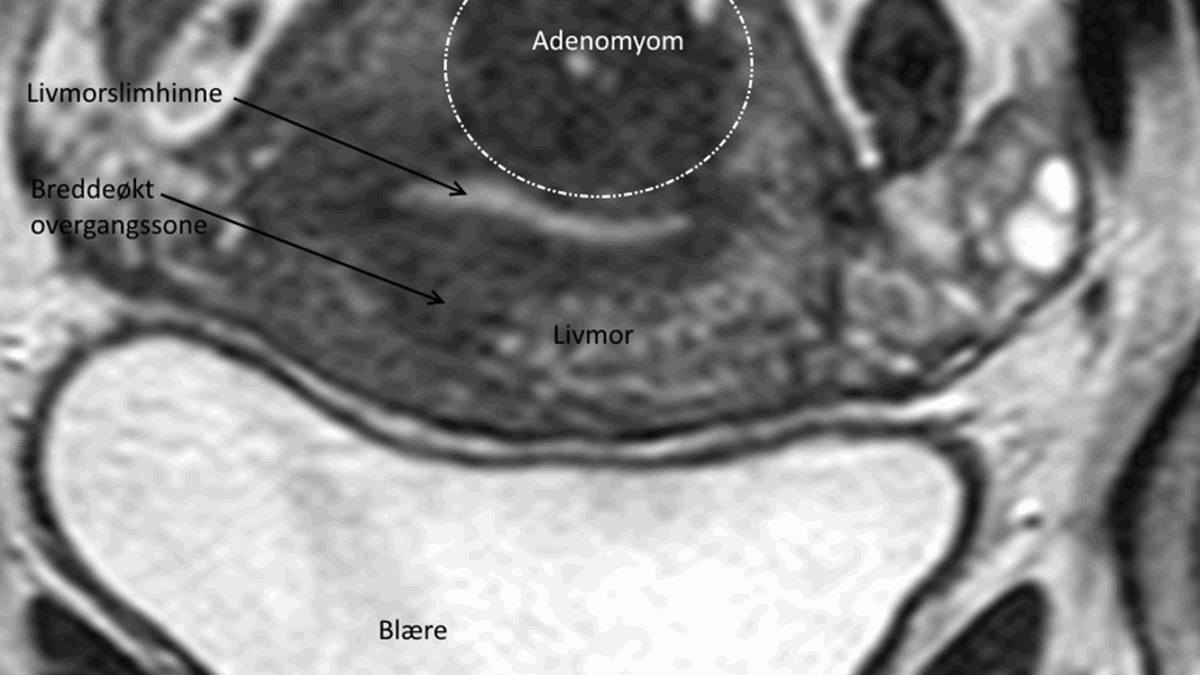

Det er også muligt at stille diagnosen ved en MR-scanning. Med denne metode kan ca. 90% af alle tilfælde blive diagnosticeret korrekt, forudsat at den rigtige undersøgelsesprotokol vælges, og at undersøgelsen bliver gennemført med god kvalitet.

Hvis lægen er usikker på diagnosen efter en indvendig ultralydsundersøgelse, kan der foretages en MR-scanning.